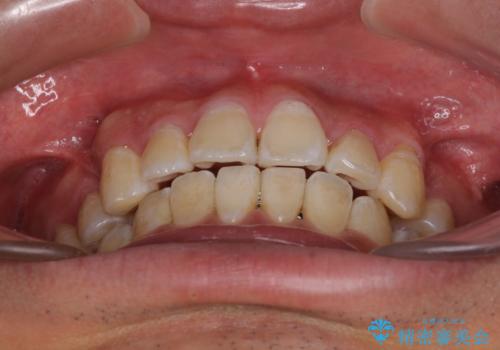

- 前歯の叢生と八重歯を気にして来院された患者様です。

叢生が強く、奥歯の咬合も左右差が大きかったため、上下左右4本を抜歯して、ワイヤー矯正を行うこととしました。